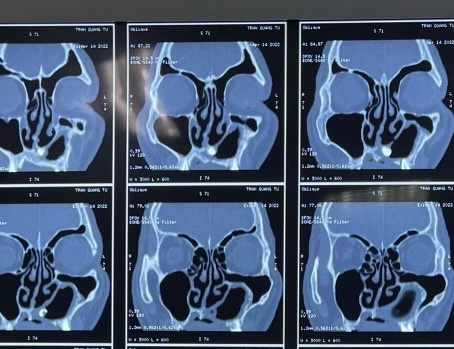

CT Scanner xoang: có hình ảnh khối cản quang (mật độ tương tự mô xương) nghi là một chiếc răng nằm trong xoang hàm.